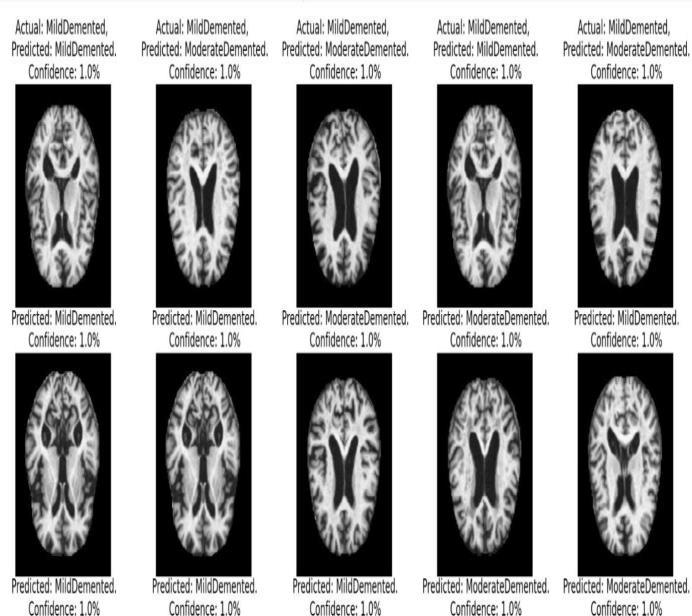

Disease classification:

OncetheAlzheimer’sdiseaseisdetected,itisthenfurther classified,thisclassificationisdonebyusingdeeplearning techniques. For the accuracy of classification, CNN Architecturesofdeeplearningareused.